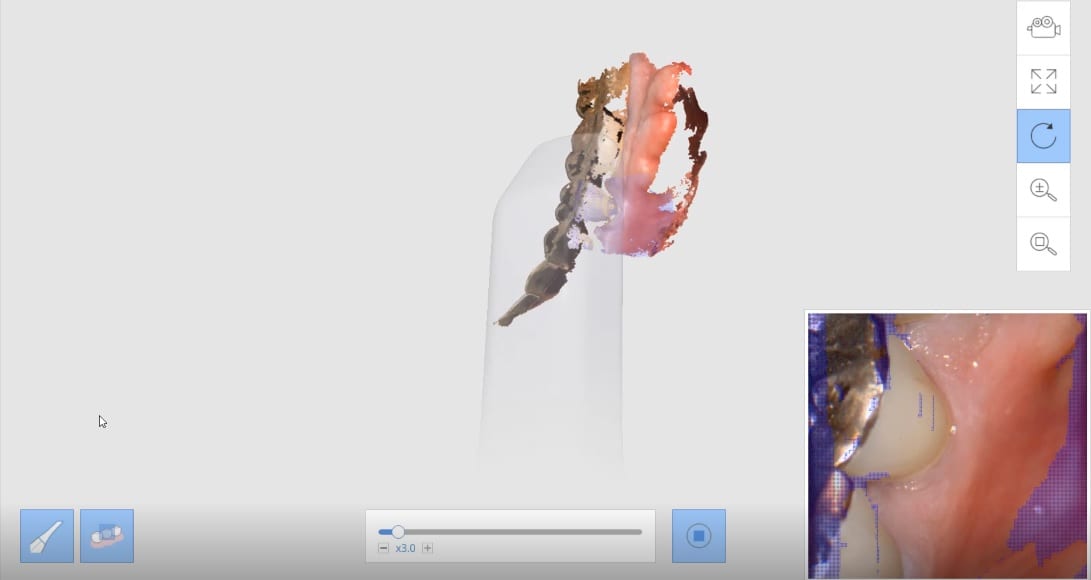

Milling A Lower Central Incisor in an eMax Size 12 Block on the VHF Z4 Milling Machine

March 29, 2019Time Stamps: This video is sped up at some points, but from the time the design was finished and it was sent to production, it tool less than 90 seconds […]